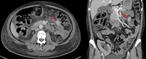

Resection of a mature cystic teratoma of the liver harboring a carcinoid tumor

Alexei A Krainev and others

Journal of Surgical Case Reports, Volume 2018, Issue 10, October 2018, rjy279, https://doi.org/10.1093/jscr/rjy279